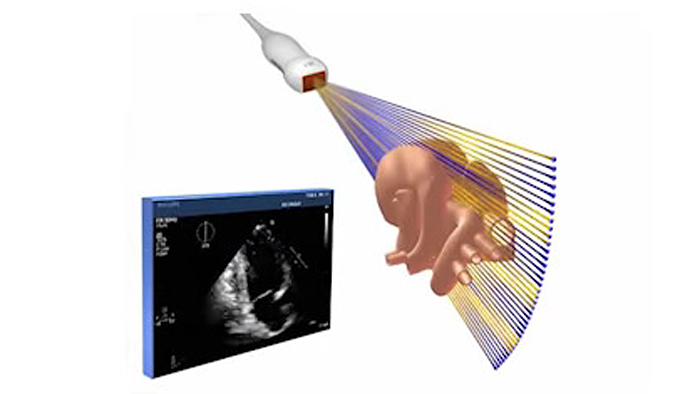

xMATRIX sorgt aufgrund der hohen Transparenz, Detailgenauigkeit und Auflösung für schnelle und einfache Untersuchungen – zum Wohl von Klinikpersonal und Patienten. Die xMATRIX Technologie ermöglicht die schnelle und einfache Volumenerfassung, unterstützt mehrere Abfragefunktionen und bietet Ansichten, die mit der 2D-Bildgebung nicht möglich sind – all dies mit außergewöhnlicher Bildqualität. Sie ermöglicht die zuverlässige Beurteilung von Anatomie und Funktion, die problemlose Erkennung von pathologischen Veränderungen und die genaue Visualisierung von strukturellen Zusammenhängen im dreidimensionalen Raum.

xMATRIX Schallköpfe setzen neue Maßstäbe in puncto Scanleistung. Sie nutzen das Potenzial von 150 Computerplatinen mit 2.500 bis über 9.000 voll abgetasteten Kristallelementen für die 360-Grad-Fokussierung und Strahlsteuerung. In Kombination mit der nSIGHT und PureWave Kristalltechnologie von Philips wird ihre Leistung noch weiter erhöht.